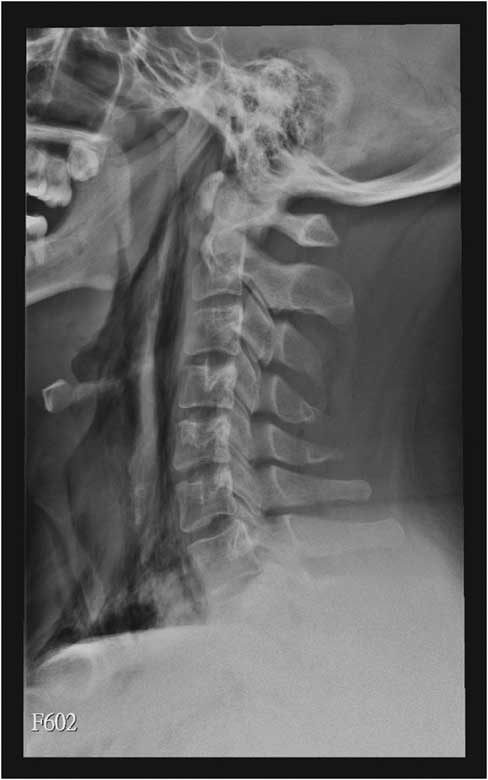

A 22-year-old male presented to the emergency department due to progressive odynophagia and dysphagia. He underwent a left third mandibular molar extraction at the dental clinic a week prior. At the emergency department, vital signs were normal except tachycardia (114/min) and tachypnea (22/min). A physical examination revealed bilateral neck tenderness with crepitus on palpation, no stridor or acute airway compromise signs. Laboratory data showed leukocytosis (white blood cell count, 19000/cumm; segmented, 91%) and elevated C-reactive protein (1.07 mg/dL). Radiographs showed the presence of prevertebral emphysema on the C-spine lateral view (Figure 1) and subcutaneous emphysema with pneumomediastinum on the chest posteroanterior view (Figure 2). A non-contrast computed tomography (CT) scan confirmed the radiographic findings; additionally, there was gas collection over the pericarotid, pericardial (Figure 3) and extradural spaces (Figure 4). Because there was no CT evidence of infectious signs and clinical features were stable, conservative treatment with intravenous amoxicillin/clavulanic acid was given for a week. Clinical symptoms improved, and a follow-up CT showed no residual gas.

Figure 3 Non-contrast chest computed tomography shows pneumopericardium (arrowhead).

Although subcutaneous emphysema is a rare complication following dental procedures, with mostly benign and self-limiting sequelae, it may progress to fatal consequences such as cardiac tamponade, air embolism, pneumothorax, and mediastinitis.Reference Goodnight, Sercarz and Wang 1 There have been reports correlating subcutaneous emphysema and dental treatments with the use of air turbine hand-pieces and air syringes.Reference McKenzie and Rosenberg 2 , Reference Arai, Aoki and Yamazaki 3 CT is useful to detect the precise extension of gas dissection, such as pneumomediastinum, pneumopericardium, and pneumorrhachis, in this case.Reference Ehmann, Paziana and Stolbach 4 Most importantly, CT can evaluate the complications of extensive emphysema or infectious process. In addition, it can guide clinical treatment decisions like the need for urgent tracheostomy or fasciotomy.